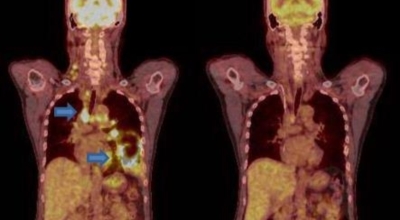

폐암 검사는 X-ray를 통해서 검사하는데 , 크기가 작거나 구석에 위치한 경우 확인이 어려운 경우도 있습니다. 그리고 조직 검사를 통해서 정확한 진단을 하게 되어요. 폐암이 발견되면 종양의 크기나 전이 여부 , 위치에 따라서 수술 여부를 결정하게 돼요.